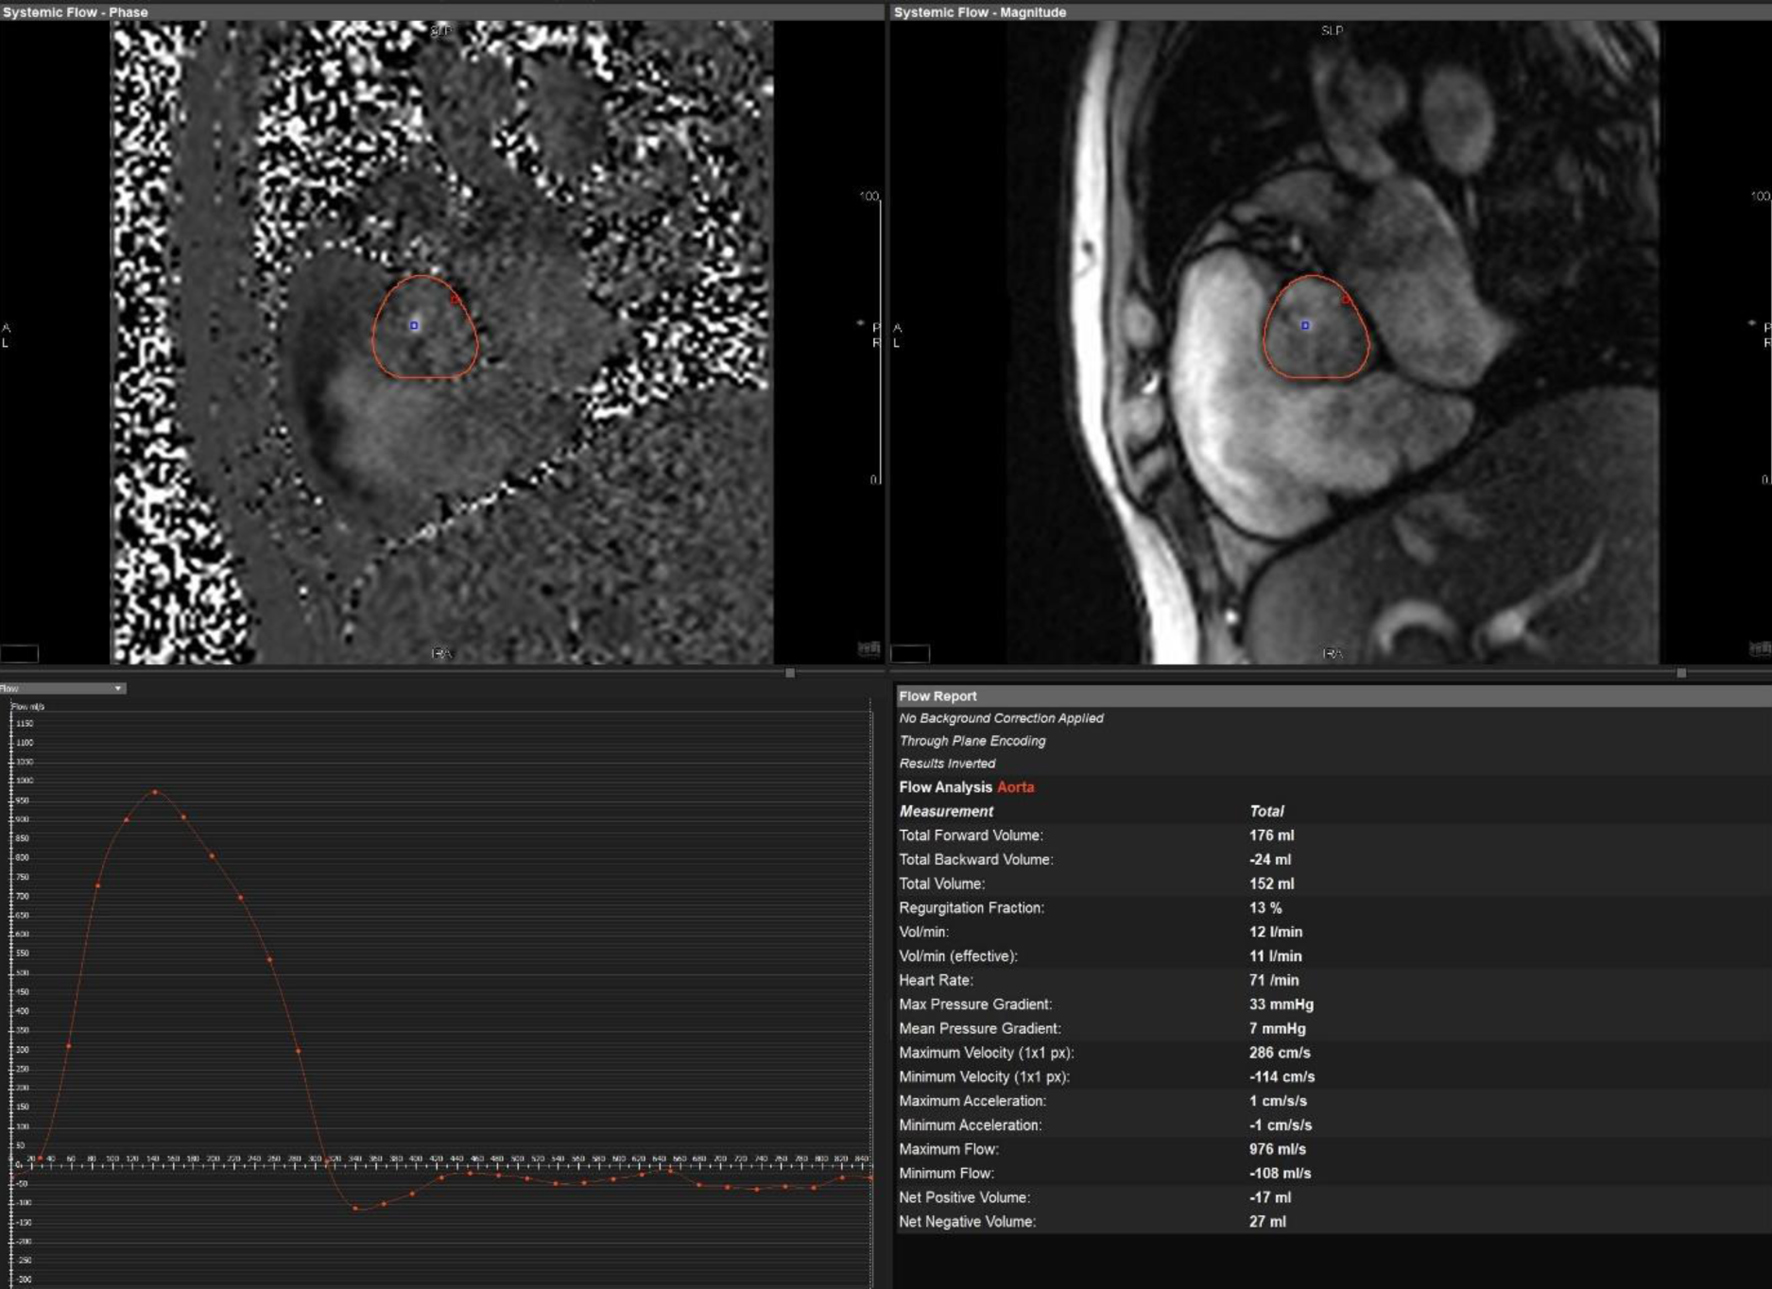

Initial bedside echocardiogram, done while intubated in ICU, showed LVEF of 30-35%, dilated LV at 6 cm, and a central jet of AR deemed moderate. Departmental TEE corroborated the impression of moderate AR. Quantitative assessment was, however, limited by eccentric AR jet (Fig. 1). Coronary angiogram showed no obstructive coronary artery disease. Two weeks later, CMRI showed a severely dilated LV with indexed end diastolic volume of 176 mL/m2 (Fig. 2). There was moderate eccentric LV hypertrophy, but preserved LVEF at 56% and stroke volume of 197 mL. Aortic valve images demonstrated a trileaflet aortic valve with partial fusion of the left and right coronary cusps, and severe AR due to failure of coaptation between these cusps (Fig. 3). Aortic regurgitant fraction was 45-50% by LV-RV stroke volume difference. Unfortunately, flow analysis was limited as the imaging plane was placed on the aortic valve rather than the sino-tubular junction, which would underestimate regurgitant fraction (Fig. 4). The AR was felt to be severe based on qualitative assessment, large, holodiastolic jet extending into LV, aortic diastolic flow-reversal, and regurgitant fraction > 45% plus LV dilatation. There was no systolic anterior motion or LVOT obstruction, and no late-gadolinium enhancement, suggesting no myocardial fibrosis, infiltration, or infarction. There was no fibrosis detected on T1 mapping. Discrepancy in LVEF between imaging modalities was explained by myocardial stunning post-arrest. AR severity was underestimated on echocardiography due to the eccentricity of the AR jet.

Figure 4. Cardiac magnetic resonance imaging showing flow across aortic valve. Malalignment of the imaging plane resulted in underestimation of the regurgitant fraction.